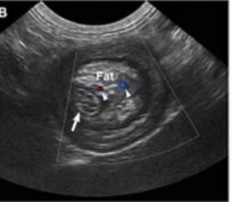

Siêu âm đóng vai trò quan trọng trong chẩn đoán bệnh viêm tử cung, các phát hiện siêu âm điển hình phù hợp với viêm tử cung bao gồm chứng to tử cung, thành tử cung dày lên, thay đổi tăng sinh nội mạc tử cung, sừng tử cung hình ống xoắn do chất lỏng gây ra, và giảm âm vang trong lòng tử cung chứa dịch. Siêu âm có thể phân biệt viêm tử cung với các mô mềm khác, khiến tử cung căng lên và là điều bắt buộc để đánh giá về sự hiện diện của tăng sản nội mạc tử cung và sự nguyên vẹn của nội mạc tử cung (Nyland & Mattoon, 2002; Wallace & Casal, 2018). Tương tự nghiên cứu Hagman (2018) khi sử dụng siêu âm để chẩn đoán bệnh viêm tử cung và tăng sản nội mạc tử cung, trên chó mắc tăng sản nội mạc tử cung quan sát thấy thành tử cung dày lên và có các cấu trúc nang không cản âm và không có dịch trong tử cung, trong khi đó với trường hợp chó vừa bị viêm tử cung và tăng sản nội mạc tử cung quan sát thấy thấy thành tử cung dày lên và có các cấu trúc nang không cản âm và quan sát dịch trong tử cung. Tương tự nghiên cứu Mattei & cs. (2018) khi thực hiện chẩn đoán trên một chó Labrador Retriever 7 tuổi chưa sinh sản được đưa đi viện vì tiền sử nôn mửa, chán ăn trong 1 ngày, đi tiểu nhiều, khát nước nhẹ và có dấu hiệu mệt mỏi, sưng âm hộ với một ít lượng dịch màu vàng. Chụp X quang bụng cho thấy một khối giãn nở chủ yếu chứa đầy khí, ban đầu nghi ngờ có tắc ruột non. Sau khi kiểm tra siêu âm phát hiện một bên sừng tử cung có vách giảm âm đồng nhất và chứa khí và chất lỏng có độ

vang trong lòng ống và chẩn đoán viêm tử cung. Siêu âm có thể được sử dụng như một phương pháp chẩn đoán không đưa vào bên trong cơ thể để phân biệt tắc ruột và tử viêm cung khí thũng.

Hình 4.24. Hình ảnh siêu âm tử cung bị viêm của giống Corgi 6 tuổi

(mũi tên)